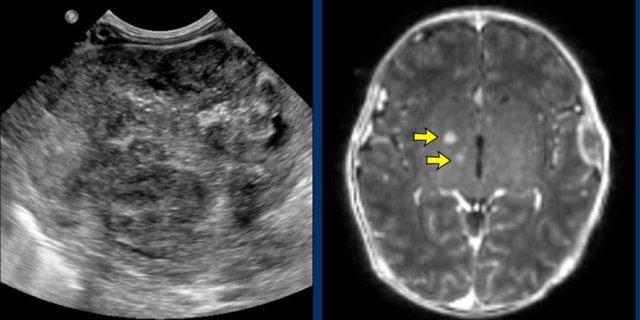

Hình ảnh minh họa

Bé gái 2 tuần tuổi nhập viện với khối u ở thận trái.

MRI não tại thời điểm chẩn đoán ban đầu cho thấy các tổn thương nhỏ, có thể là di căn (mũi tên).

MRI thực hiện bốn tuần sau đó cho thấy nhiều tổn thương di căn não và hộp sọ.

Bệnh nhân tử vong hai tuần sau đó.